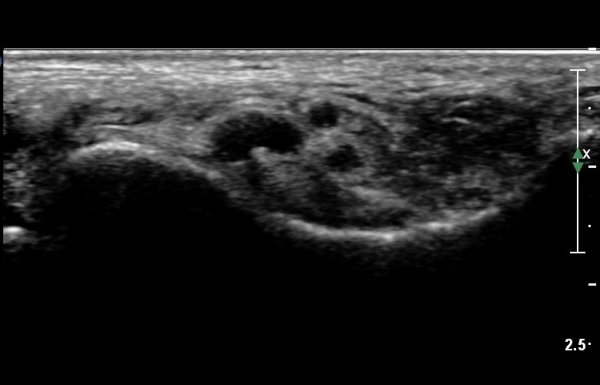

ŽÃËÀÚ¸¦ Á¶±Ý ´õ ¸»´ÜÀ¸·Î À̵¿ÇÏ´Ï Á¶±Ý¸¸ ³¶Á¾ÀÌ µÎ ½Å°æ »çÀÌ¿¡¼­ °üÂûµÈ´Ù(»çÁø 3).